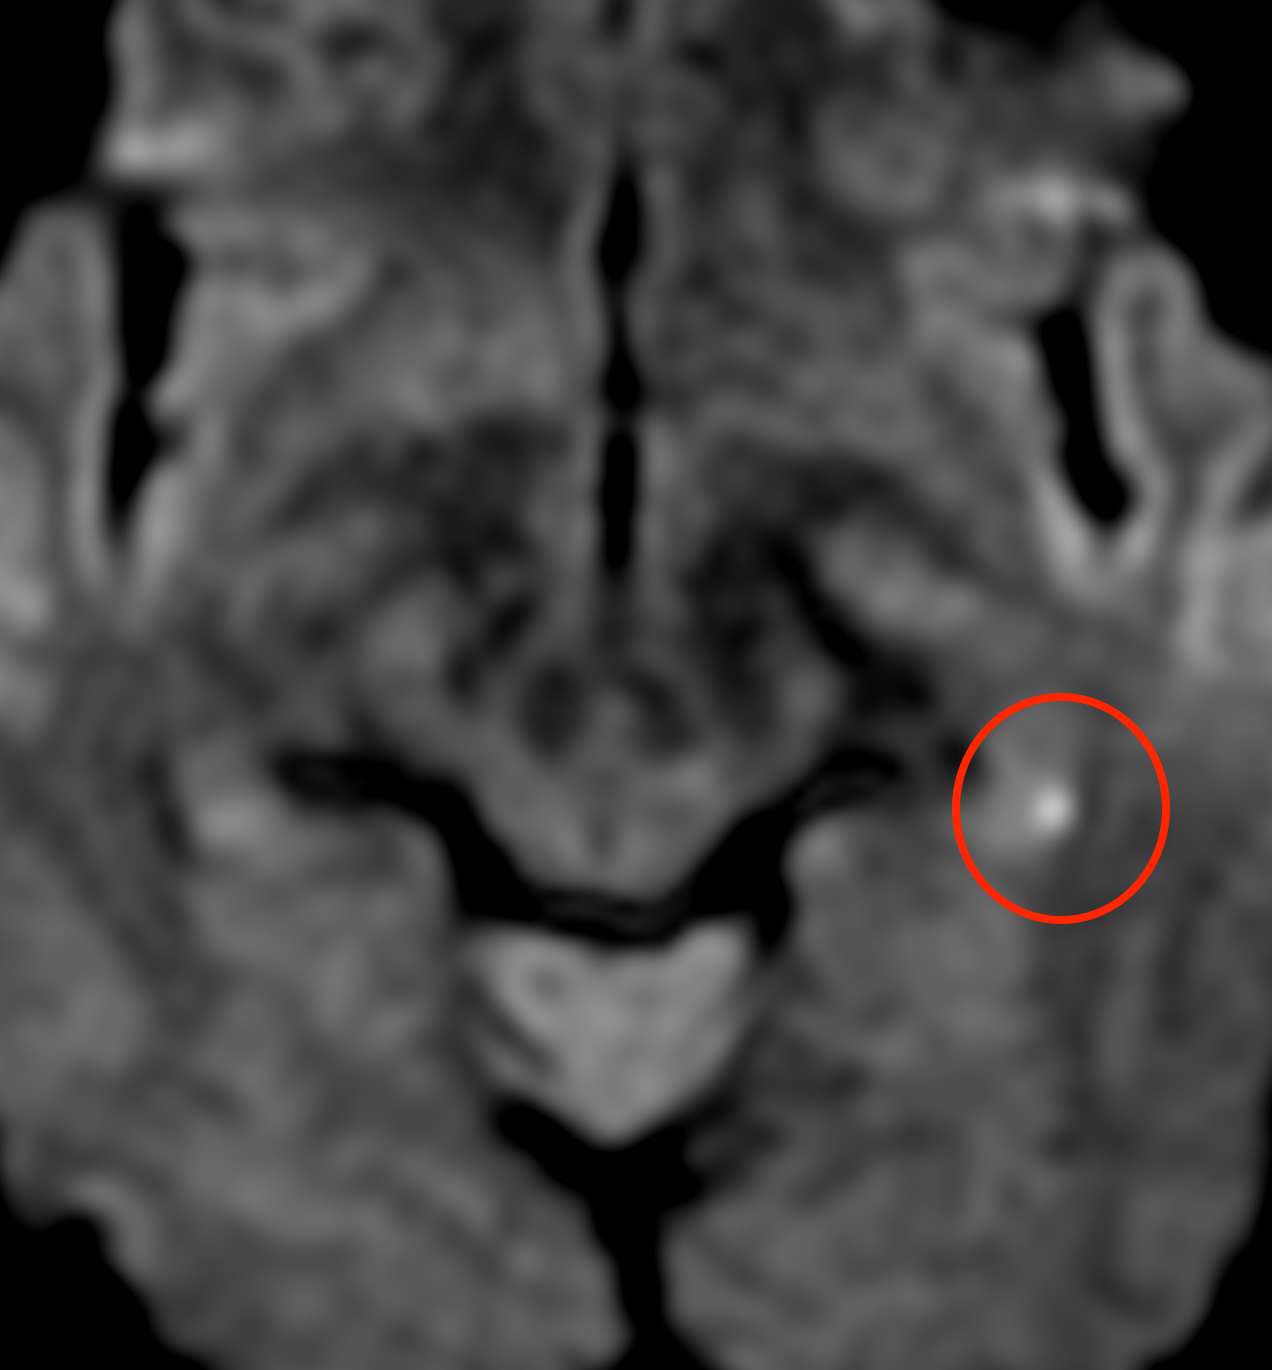

MRI検査(拡散強調画像)を見たところ、

左の海馬(記憶に関係する場所)に白く光っている部分があり、きわめて小さな脳梗塞と考えられました。

このMRI画像所見から、一過性全健忘と診断しました。

MRI検査(拡散強調画像)を確認すると、

右の海馬に白く光っている部分があり、やはり微小な脳梗塞と診断しました。